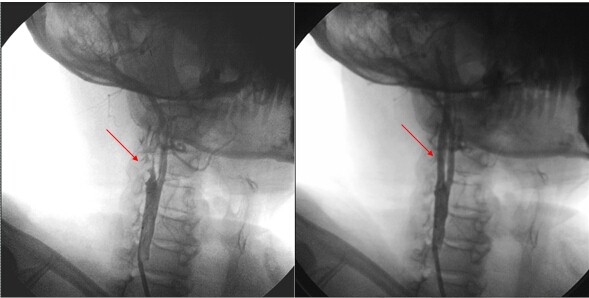

颈动脉支架术(CAS)前后血管变化(红色箭头显示血管狭窄处血流恢复)